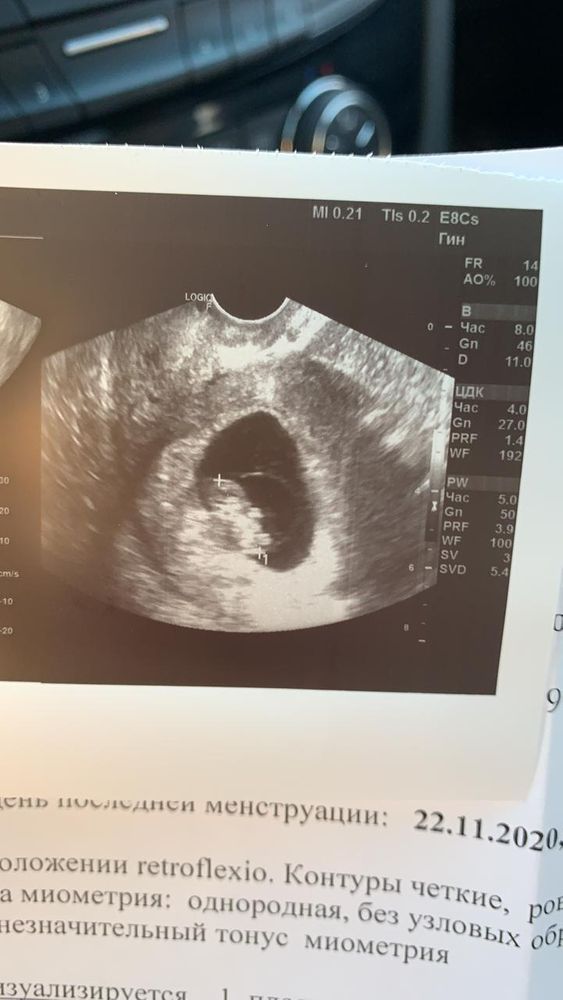

Может кто умелец по методу Рамзи определить пол?)

Всё ещё зависит, как делали узи: по животу или трансвагинально. И если справа, то девочка, слева -мальчик, но быаает и спорно.

Светлана Никиткова, оба узи трансвагинальные

Метод этот не даёт 100% гарантии. Но если на первых фото делали УЗИ трансвагинально, то, похоже, девочка.

Юлия Sonnце, обе фото трансвагинально. У меня 2 дочери уже есть😂

Метод определения пола Рамзи, вроде бы, актуален до 7 недель что ли. На втором, как понимаю, уже позже. Знаю здесь девочек, у которых не совпадало.

Юлия Sonnце, я почитала по нему, с 6 недели можно смотреть, а срок до не видела. В 12 недель уже на узи видео будет скорее всего, поэтому в нем просто смысла не остаётся)